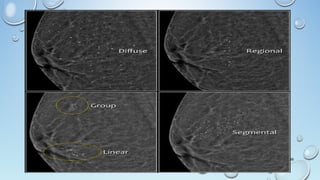

MASS

A 'Mass' is a space occupying 3D lesion seen in two different

projections.

If a potential mass is seen in only a single projection it should be called

a 'asymmetry' until its three-dimensionality is confirmed.

Shape: oval (may include 2 or 3 lobulations), round or irregular

Margins: circumscribed, obscured, microlobulated, indistinct,

spiculated

Density: high, equal, low or fat-containing.